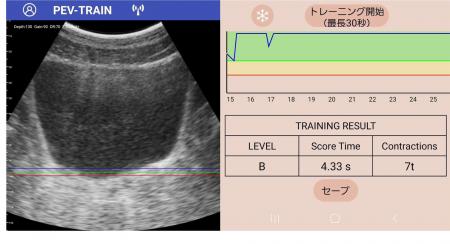

▲専用アプリで見た骨盤底筋の様子と、トレーニング結果を示すデータ

「PEV・TRAIN -ぺブトレ」は、ポータブル超音波エコーとスマホアプリが連動しているため、従来の正しくトレーニングが行えているか分からない、どのくらい筋力が増えたか効果が見えにくいといった課題を解決し、誰でも簡単・正確にトレーニングができる新しい仕組みを提供します。

- 「スマホで自分の骨盤底の動きを見ながらトレーニング」 ポータブルエコーとアプリが連動し、視覚的に確認しながら正しくトレーニング可能。- 「アプリが自動で効果を計測」 「収縮幅」「収縮時間」を自動レコーディングし、トレーニング成果を一目で把握。- 「自宅で誰でも簡単に実施」 従来はクリニック限定だった超音波エコーを使用した骨盤底トレーニングを個人向けのトレーニングアプリとして新たに開発。自宅やジムで活用可能に。- 「専門医監修の安心メソッド」 日本泌尿器科学会認定専門医・指導医で女性医療クリニック・LUNAグループの理事長でもある関口由紀医師(医学博士)が監修。